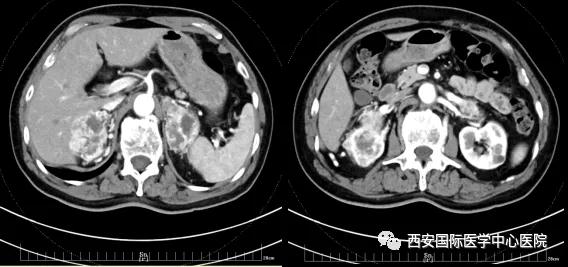

今年七十五歲的患者,來自陜西省商洛市,四月前因腰背部疼痛就診于當(dāng)?shù)蒯t(yī)院,行CT檢查發(fā)現(xiàn)“右腎、雙側(cè)腎上腺占位,前縱膈淋巴結(jié)腫大,雙肺多發(fā)結(jié)節(jié)、胸椎骨質(zhì)破壞,考慮轉(zhuǎn)移瘤”。為進一步診斷治療,患者的兒子帶他來到西安某三甲醫(yī)院,查泌尿系CT提示“右腎占位性病變,多考慮腎癌,雙側(cè)腎上腺多發(fā)轉(zhuǎn)移灶,腹膜后多發(fā)腫大淋巴結(jié)”;行穿刺活檢提示“腎透明細胞癌”;并給予患者口服靶向藥物的治療方案。

自四月份至今,患者一直口服靶向藥物治療(阿昔替尼5mg 2次/日),期間無不良反應(yīng),目前腰背部疼痛癥狀也有所緩解,復(fù)查影像學(xué)資料提示瘤體較前縮小,腫瘤完整切除的可能性明顯提高;而且患者的兒子也是一名外科醫(yī)生,所以他更想為父親完成后續(xù)的手術(shù)治療。

手術(shù)由楊增悅教授主持,舒濤主治醫(yī)師、王東主治醫(yī)師主刀,黃怡醫(yī)師、王平醫(yī)師協(xié)助完成。由于第四代達芬奇機器人更加靈活和精準(zhǔn)的特性,手術(shù)全程順利,尤其是完全精準(zhǔn)的“解鎖”了右腎動脈和右腎靜脈的數(shù)十根交互纏繞的分支血管。術(shù)后患者麻醉恢復(fù)后生命體征平穩(wěn),順利返回泌尿外科普通病區(qū)進一步康復(fù)。